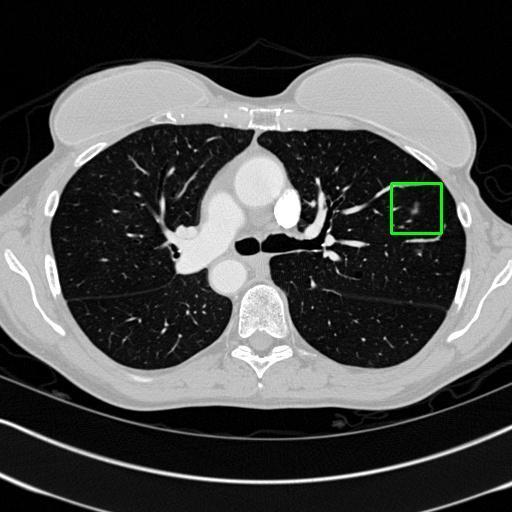

We developed an AI-based system using deep learning models for analyzing lung CT scans to detect and classify pulmonary nodules. We chose the YOLOv11 architecture for its enhanced object detection capability and adapted it specifically for medical imaging, incorporating pixel-level precision and severity classification.

Classification into three severity levels with colored bounding boxes.

Designed a severity classification system that categorizes nodules into null, moderate, and severe using colored bounding boxes, assisting in rapid clinical decision-making.